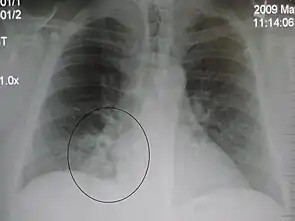

The discovery of x-rays made it possible to determine the anatomic type of pneumonia without direct examination of the lungs at autopsy and led to the development of a radiological classification. Early investigators distinguished between typical lobar pneumonia and atypical (e.g. Chlamydophila) or viral pneumonia using the location, distribution, and appearance of the opacities they saw on chest x-rays. Certain x-ray findings can be used to help predict the course of illness, although it is not possible to clearly determine the microbiologic cause of a pneumonia with x-rays alone.